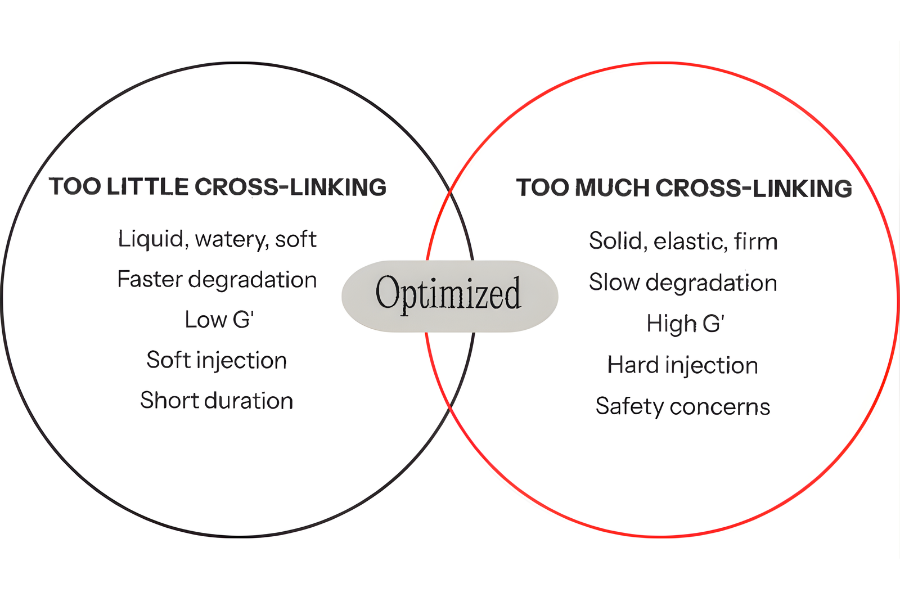

Thixofix® Technology: Balanced Rheology

Revanesse® is built on Thixofix® cross-linking technology, combining:

- High molecular weight HA

- Low cross-linking agent (BDDE)

- Homogeneous, round particle distribution

The result is a gel with balanced viscoelastic properties, allowing:

- Controlled flow under pressure

- Stability at rest within tissue

- Precision placement across superficial and deep planes

Optimised for your technique, not against it.